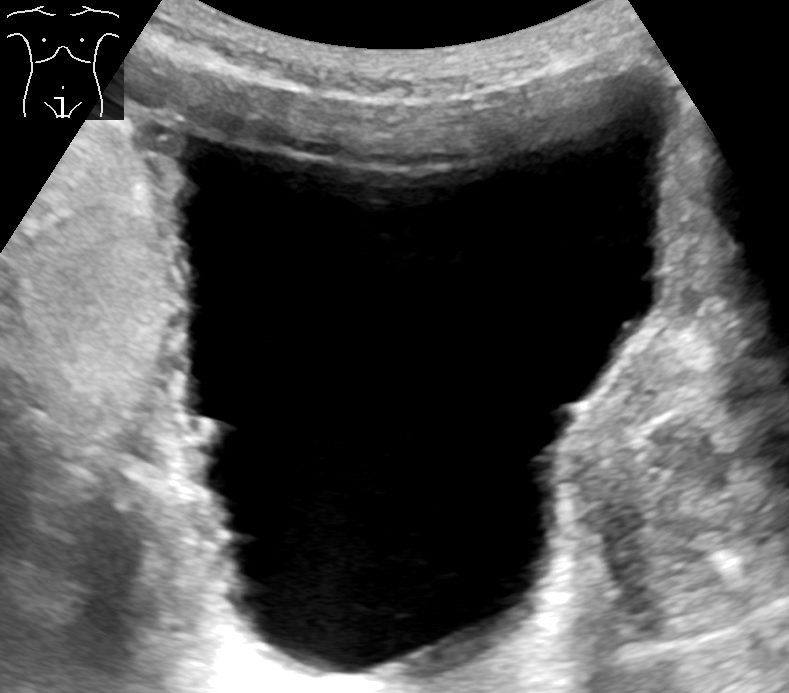

뇨류를 분석하면 배뇨 이상의 유형을 판단하는 데 도움이 될 수 있다. 방광 초음파를 통해 흔히 진단되는 것들로는 느린 속도의 뇨류, 간헐적인 뇨류, 배변 후에도 방광 내에 잔재하는 상당한 양의 오줌이 있다. 정상 시험 결과는 초당 최고 20ml~25ml의 뇨류 속도를 보인다. 배뇨 후 남은 소변이 50ml를 초과하는 경우 상당한 양으로 간주되며 요로감염증이 재발할 가능성을 높인다. 60세 이상의 성인의 경우 50ml~100ml의 잔여 소변은 방광의 용적을 증대시킨다. (정상 용적은 400ml~600ml)

만성 요폐의 경우 방광 초음파 검사에서 방광 용량의 대규모 증가를 보일 수 있다. 비신경성 만성 요폐는 표준화된 정의가 없지만, 300ml 이상의 소변량이 비공식적인 지표로 사용될 수 있다.[8] 요폐 진단은 6개월 동안 진행되며, 6개월 간격으로 2번의 소변량 측정이 이루어진다. 측정 결과는 배뇨 후 잔뇨량(PVR)이 300ml 이상이어야 한다.[8]